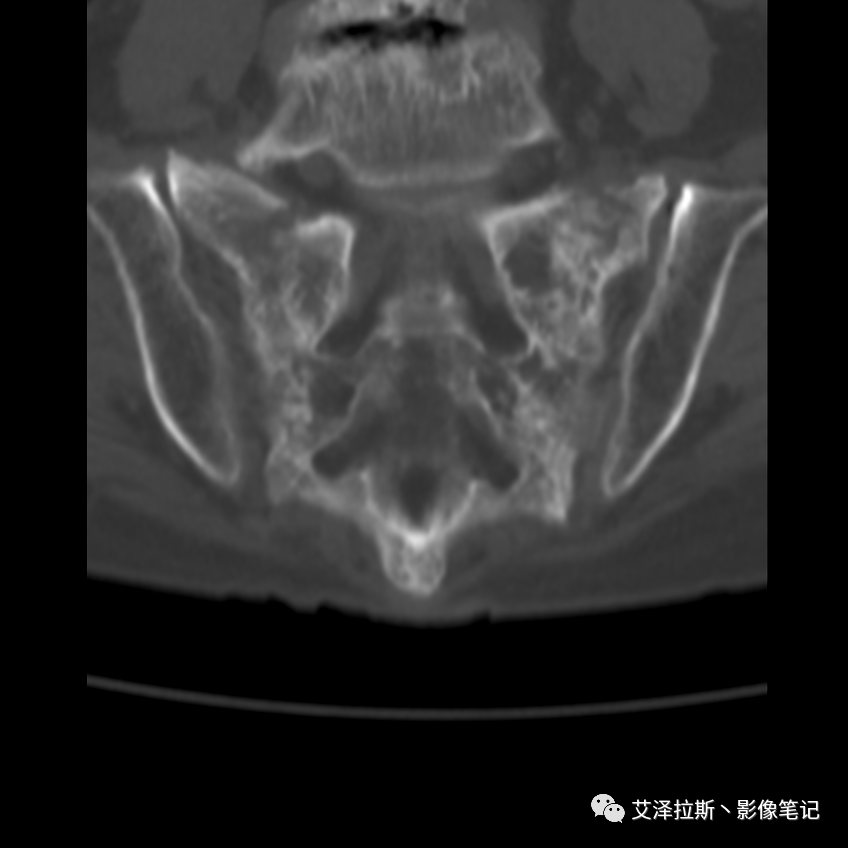

病例2:患者,女性,69岁,老年性骨质疏松症。

CT平扫:

X线、CT:骶骨重度骨质疏松,双侧骶骨翼皮质断裂,分别见迂曲走行的纵行透亮线位于骶孔外侧,大致与骶髂关节间隙平行,骨折端局部可见骨痂、骨质硬化。

骶骨功能不全骨折

①单侧或者双侧骶骨翼骨折,典型者呈“H”形,即“Honda征”;

②骨折线位于骶孔外侧(如下图,主要发生于1区),通常可能会伴随耻骨的功能不全骨折(如:病例2 右侧耻骨上支骨折,L5双侧横突骨折);

③愈合期骨折线模糊,骨痂形成,骨质硬化;